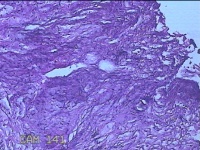

右侧卵巢囊肿

性别

女

年龄

19岁

临床诊断

一般病史

下腹痛1小时。

标本名称

大体所见

灰白暗红色囊壁样组织11x4.5x2.3cm两块,表面糜烂,因已切开,囊内容物已流失,囊壁厚0.1cm。